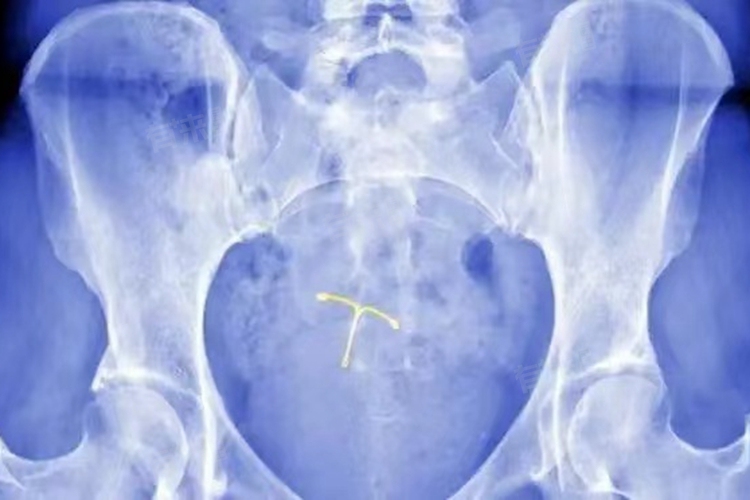

上环即放置宫内节育器,是一种常见的避孕方式,但也可能存在一些危害和副作用,如阴道不规则出血、腰酸、腹坠、感染、节育器移位或嵌顿等。

4、节育器移位或嵌顿:节育器可能会因为子宫收缩、放置位置不当等原因发生移位,甚至部分或全部嵌入子宫肌层。节育器移位可能导致避孕失败,而嵌顿则可能引起更严重的后果,如子宫穿孔等,需要通过手术取出节育器。

此外少数女性可能对节育器的材料过敏,出现过敏反应,如外阴瘙痒、皮疹等。上环后还可能影响月经周期,导致月经紊乱。如果在上环后出现上述严重不适症状,或者症状持续不缓解,建议及时就医,进行相关检查,如超声检查等,以确定节育器的位置和身体状况,并采取相应的治疗措施。